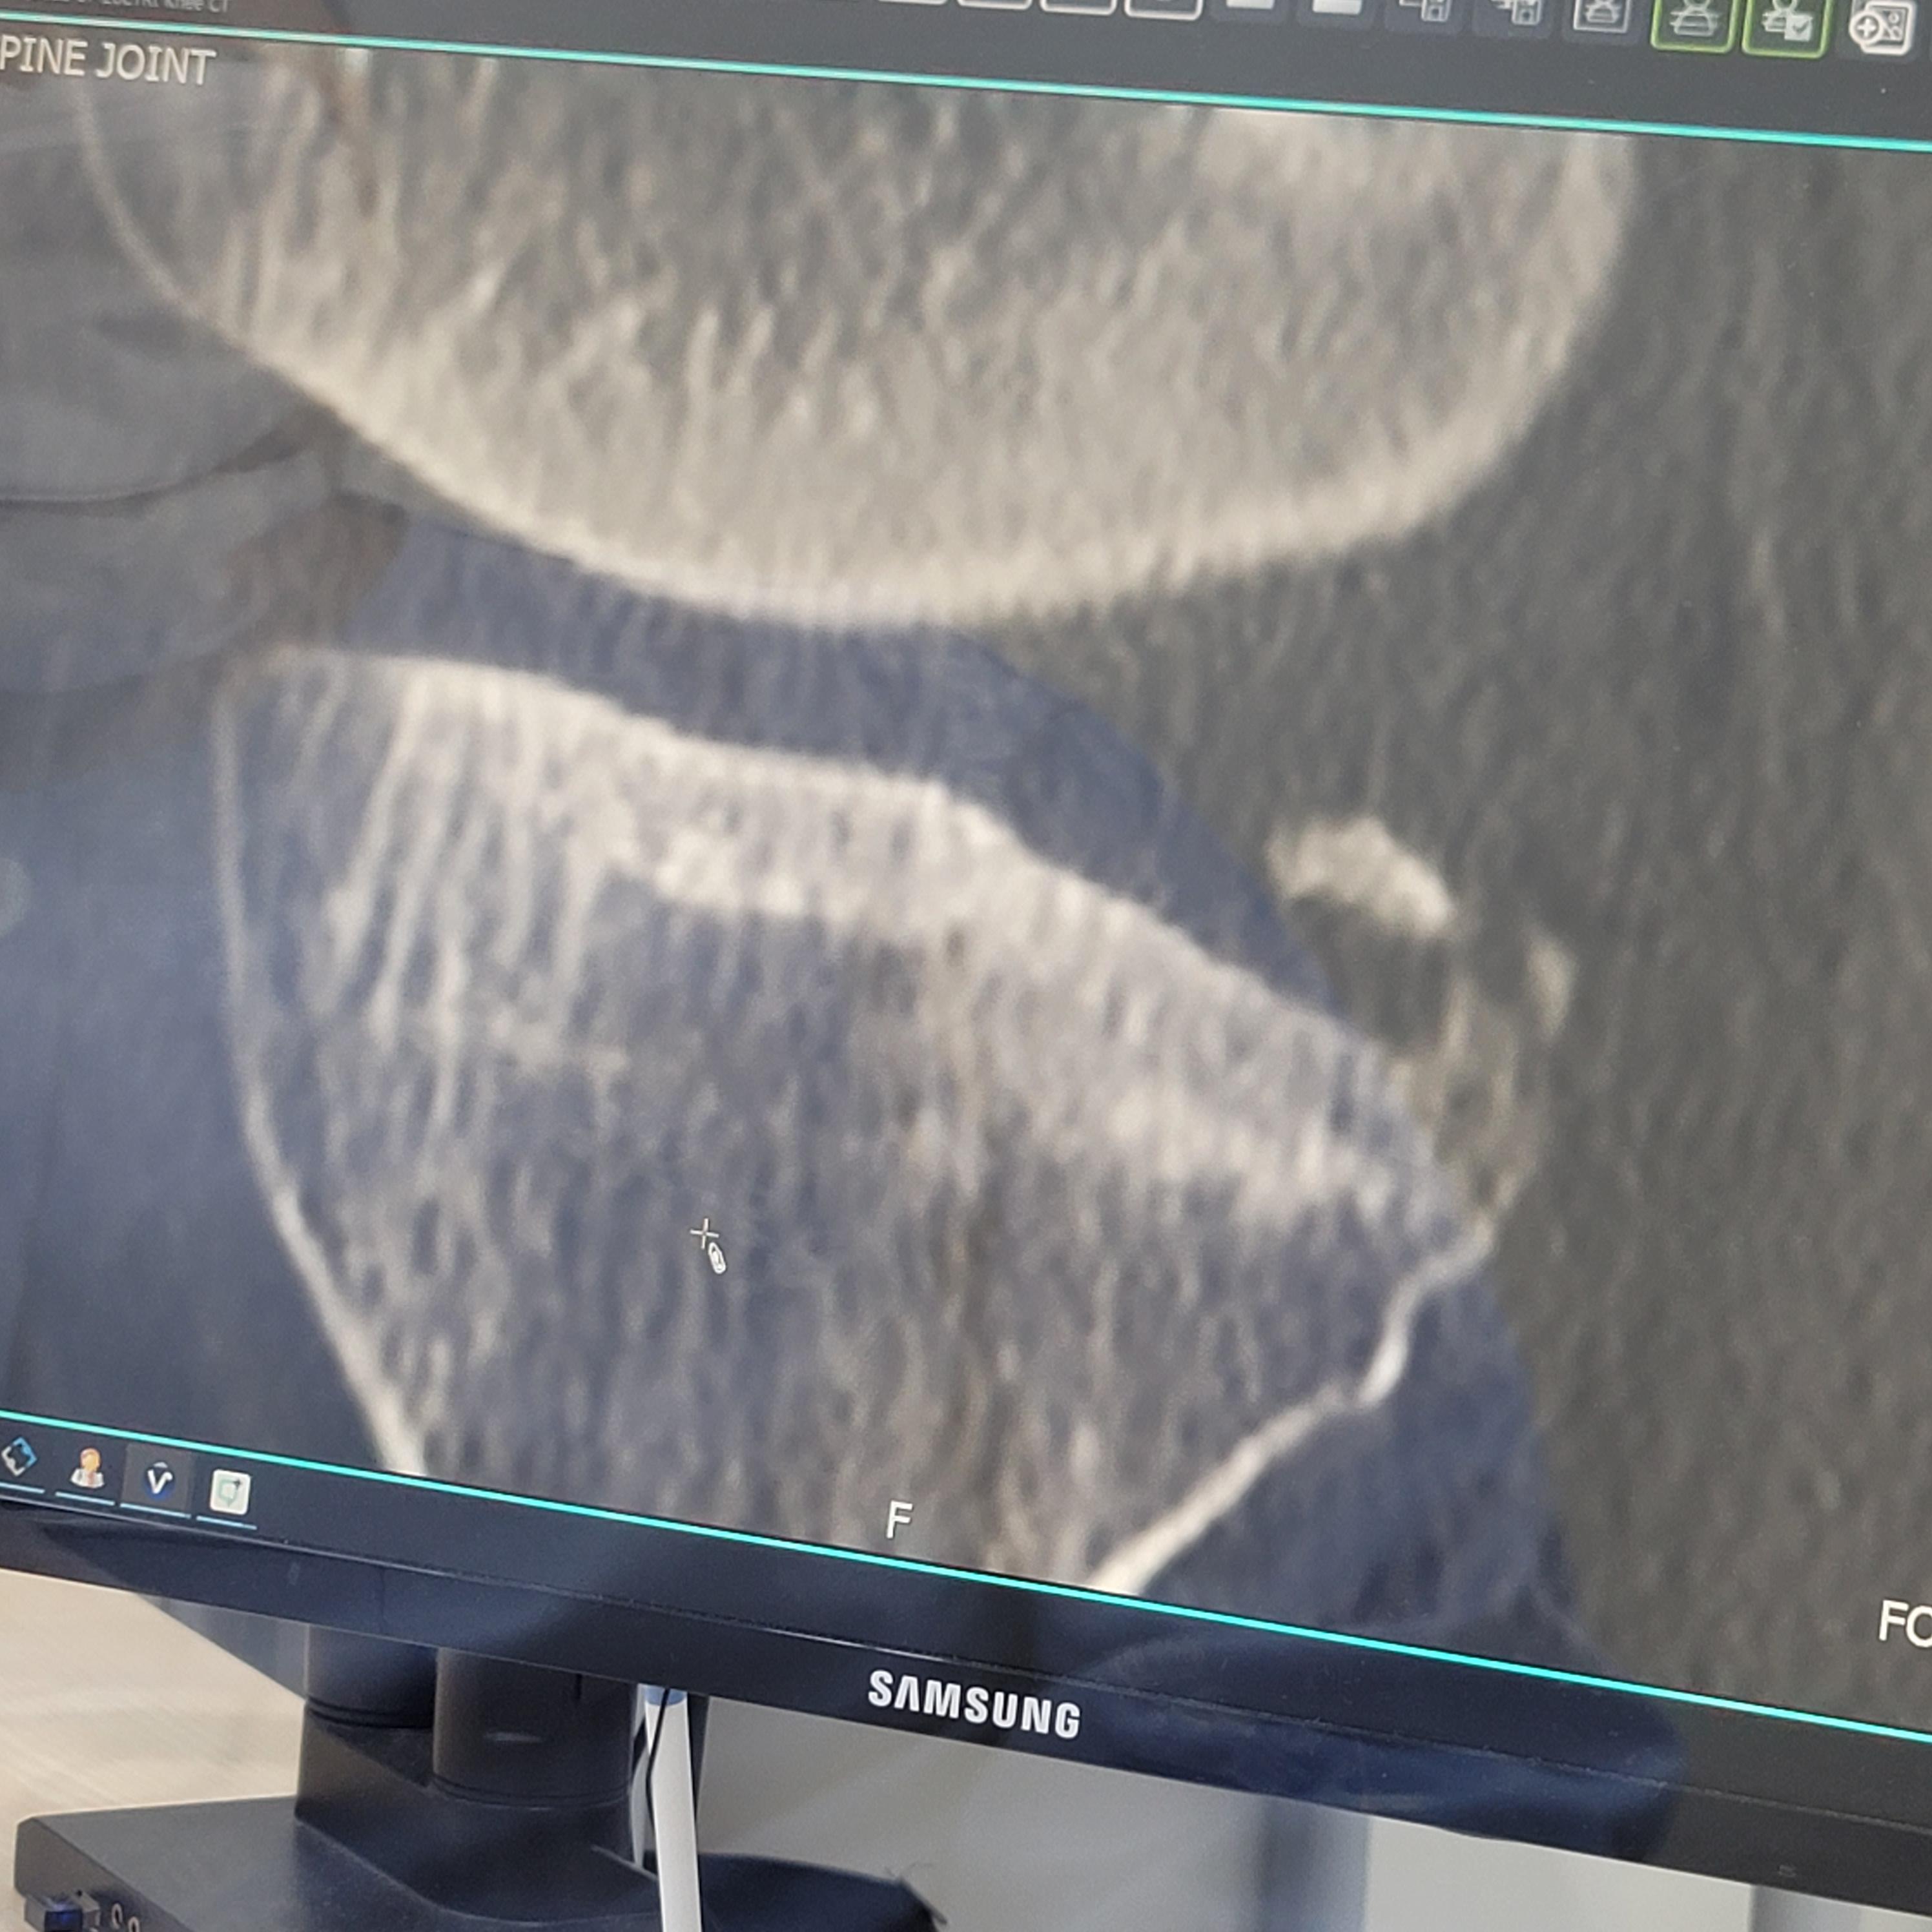

오빠는 무릎이 너무 아프다고 했다.

그래서 무릎을 중점적으로 엑스레이

엑스레이 후 좀 더 정밀검사가 필요하다고

하셔서 CT를 찍었고 좀 더 정밀검사가

필요하다고 하셔서 MRI를 추가로 찍었다.

전방 십자인대 거의 다 날아갔고

연골판 뒤쪽 뿌리 부분이 찢어져서

둘 다 수술을 진행해야 하는 상황이며

수술은 1시간 30분 걸리고

하반신 마취로 수면 수술을 한다 했다.

다른 병원에 엑스레이, CT, MRI 시디

들고 갔는데 수술해야 하는 이유가

2가지가 아니라 3가지라고 하셨다.

1가지 이유가 더 있었던 것이다!